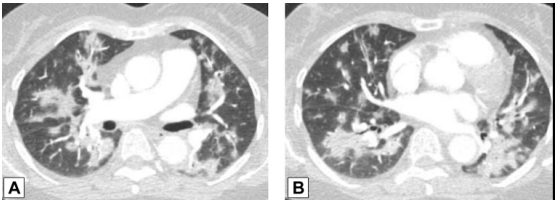

在活检证实的OP患者中,中肺(图2A)和下肺(图2B)的增强CT扫描图像显示双侧多灶性支气管血管周围实变灶。

图2 支气管血管周围实变